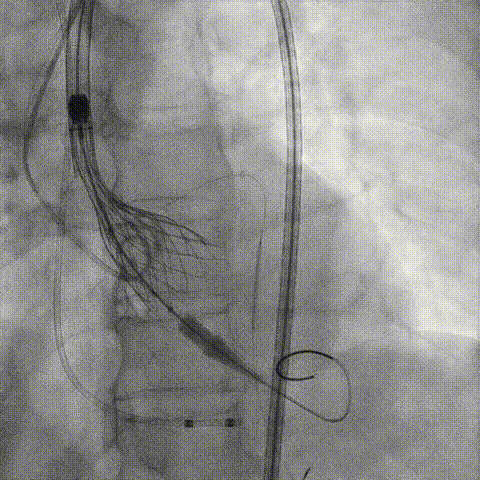

预置Telescope™导引延长导管及导丝保护左冠,

18mm球囊预扩张再次评估冠脉闭塞风险。

Telescope™+Runthrough

18mm*40mm 预扩张

预埋 Resolute Integrity 3.5*26mm

再次评估左冠开口